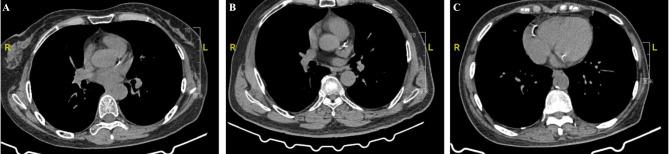

A total of 9585 participants who underwent computed tomography (CT) screening for lung cancer from 2018 to 2020 were included in this cross-sectional study. Demographic data, laboratory test data and medical history data were collected from medical records. TYG = Ln[fasting glucose (mg/dL)×fasting TG (mg/dL/2]. The triglyceride glucose-HDL-c ratio was calculated as TYG/HDL-c. CAC was evaluated on chest CT images. Multivariate logistic regression analysis and restricted cubic splines were used to determine the relationships among the TYG index, TYG/HDL-c ratio and risk of CAC. The receiver operating characteristic (ROC) curve was used to evaluate the performance of the TYG index and TYG/HDL-c ratio in identifying CACs in individuals aged 60 years and above.

CAC was detected in 2515 of 9585 participants (mean age 51.8 ± 15.5 years, 61.2% men). The prevalence of CAC was significantly greater in participants with a high TYG/HDL-c ratio (32.6% in the fourth quartile vs. 19.1% in the first quartile, p < 0.001). Multivariate logistic regression revealed that both the TYG index (odds ratio (OR) = 1.06, 95% confidence interval (CI): 1.02-1.10) and the TYG/HDL-c ratio were associated with coronary artery calcification (OR = 1.32, 95% CI: 1.14-1.51). No such association was observed between the TYG index and CAC when further adjusted for the serum lipid level (OR = 1.23, 95% CI: 0.99-1.54). The TYG/HDL-c ratio was still associated with CAC after further adjustment for low-density lipoprotein cholesterol and total cholesterol (OR = 1.21, 95% CI: 1.09-1.35). TYG/HDL-c ratio was associated both with single vessel and multivessel calcification (OR = 1.14, 95%CI:1.05-1.23; OR = 1.15, 95%CI: 1.05-1.21). Similar trends were observed when we categorized individuals by TYG index and TYG/HDL-c quartiles and in subjects older than 60 years. Restricted cubic splines revealed that the TYG/HDL ratio had a better dose‒responsive relationship than did the TYG index. Subgroup analysis revealed that the association between the TYG/HDL-c ratio and coronary artery calcification was mainly observed in nondiabetic or nonhypertensive participants, regardless of low-density lipoprotein cholesterol levels. The ROC curve also revealed that the TYG/HDL-c ratio was better able to identify CAC than the TYG index was (area under the curve = 0.54 vs. 0.52, p < 0.01) in subjects older than 60 years.